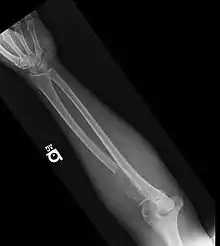

- Bone lesions: one or more osteolytic lesions on skeletal radiography, CT, or PET/CT. * (If bone marrow has less than 10% clonal cells, more than one bone lesion is required to distinguish from solitary plasmacytoma with minimal marrow involvement.)

Radiology | Normal bone X-rays or solitary bone lesion | advanced lytic bone lesions ("extensive skeletal destruction and major fractures") | |